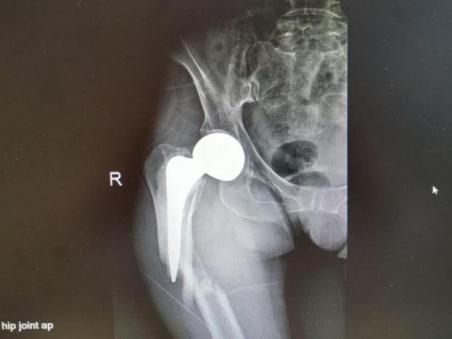

2025年11月1日,由遵义市医学会手外科分会主办、遵义市第二城市医疗集团(贵州航天医院)承办的遵义市医学会手外科分会学术交流会暨贵州省继续医学教育项目《急诊手外伤治疗临床研究新进展专题研讨班》在贵州航天医院成功举办,汇聚了遵义市手外科领域专家及基层医疗骨干,通过专题研讨与临床经验分享,共探急诊手外伤诊疗新进展。 会议特邀遵义市医学会手外科分会主任委员金文虎教授,遵义市医学会手外科分会副主任委员张子阳教授,遵义市医学会手外科分会常务委员杨绍浦教授,贵州航天医院陈明勇教授、赵兴东教授等遵义市手外伤专家进行交流分享;贵州航天医院党委委员、副院长彭亮参加会议并致辞,贵州航天医院骨科医务人员,遵义市第二城市医疗集团成员单位及红花岗区、绥阳县、桐梓县等区县医疗机构手外伤骨干参与。 贵州航天医院党委委员、副院长彭亮致辞 学术交流 本次学术交流以“急诊手外伤治疗临床研究新进展”为主题,通过理论授课与临床案例结合,共同探讨急诊手外伤临床诊疗全链条诊疗策略、关键技术、临床研究新进展,促进规范化诊疗技术向基层下沉,助力提升区域手外伤应急处置与修复能力。 贵州航天医院赵兴东教授分享《急诊手外伤的诊断与治疗原则》 贵州航天医院陈明勇教授分享《开放性骨折的治疗原则》 贵州航天医院张军教授分享《甲沟炎Winograd手术的临床应用》 贵州航天医院赵兴东教授分享《手部常见的皮肤缺损及治疗原则》 贵州航天医院张艳金教授分享《开放性骨折的清创术》 贵州航天医院冷家雄教授分享《下肢创面修复的常用皮瓣之股前外侧皮瓣》 贵州航天医院邬夏荣教授分享《踝关节慢性不稳的诊治》 贵州航天医院卢懿明教授分享《掌骨骨折》 贵州航天医院张艳金教授分享《手部肌腱的解剖与修复方法》 本次研讨班为遵义市手外科领域医务人员提供了深度交流契机,强化了医疗机构间的协作网络,进一步推动学科创新与临床实践融合,为健康遵义建设注入新动能。 贵州航天医院骨科专家简介 陈明勇 骨一科主任,副主任医师 临床擅长:从事创伤骨科工作约20年,对骨缺损、骨不连、骨肿瘤、肢体畸形等的肢体矫形重建及功能重建,慢性化脓性骨髓炎的根治治疗、糖尿病足的保肢治疗、快速康复理念(ERAS)下的老年骨折的诊治,四肢复杂骨折的诊治,四肢骨折等微创手术治疗具有丰富的临床经验。 2004年毕业于遵义医学院临床专业,曾在中国人民解放军总医院、广西医科大学第一附属医院、上海第六人民医院骨科进修。中国中西医结合学会骨伤科专业委员会横向骨搬移治疗糖尿病足及微血管网再生学组首届委员,遵义市医学会创伤分会常务委员。 瞿 晖 骨科党支部书记,骨二科主任,副主任医师 临床擅长:对骨科的常见病、关节外科、脊柱外科及运动医学疾病的诊治具有丰富的临床经验,熟练掌握骨科手术操作技术。 毕业于遵义医学院临床医学系,2005年前往广州中山大学第一附院骨显微医学部进修学习,2011年前往成都华西医院进修学习,并多次在省内外学习骨科相关知识,是中华医学会骨科分会会员。 赵小锋 中共党员,骨二科副主任,副主任医师 临床擅长:从事骨科临床工作11年,对骨科常见病、多发病诊疗有较为丰富的临床经验,擅长脊柱相关疾病诊断及治疗,尤其是颈、腰、腿疼痛疾病诊断及治疗,擅长胸腰椎骨折微创经皮穿刺内固定术、经皮穿刺椎体成形术、经皮穿刺脊柱内镜下腰椎间盘摘除术、单纯开创腰椎间盘摘除术、腰椎滑脱复位椎间植骨椎融合内固定术、腰椎管狭窄减压融合内固定术及人工髋、膝关节置换术等。 2012年毕业于遵义医学院外科学专业硕士研究生,2019年参加“遵义市115医学人才精英计划”于上海交通大学第一附属医院培训学习,2023年于北京大学第三人民医院脊柱外科进修学习,曾获得遵义市优秀医师荣誉称号。 遵义市手外科第一届委员,遵义市医学会创伤分会第一届委员,遵义市医学会创伤分会第二届委员,贵州省康复医学会第三届脊柱脊髓专业会委员,遵义市医学会烧伤与整形外科学分会委员,发表论文5篇,其中国家级核心期刊1篇,SCI论文1篇,主持市级课题1项并结题,参与市级课题2项。 赵兴东 骨科主任医师 临床擅长:擅长骨科的常见病及各种创伤、四肢骨折创伤修复、骨感染、手足疾病的诊治和手足体表畸形的矫形整复,熟练掌握骨科四肢骨病及创伤的手术操作技术,尤其在四肢关节复杂性损伤、手足外伤、组织缺损创面、难治创面的皮瓣修复方面及平足、高弓足矫形方面及四肢慢性疼痛诊治、康复方面具有丰富的临床经验。 硕士研究生,毕业于遵义医学院临床外科系,2015年前往山东省立医院手足外科进修学习;遵义市医学分会创伤分会第一、二届委员,遵义市手外科医学会第二委届员会常务委员;在省级及省级以上期刊发表文章9篇,参编著作2部,参与主持并完成市级课题1项,参与市级课题2项、省级课题1项。 张艳金 中共党员,骨科副主任医师 临床擅长:从事骨外科工作16年,对复合伤、多发伤的救治、四肢骨干骨折、关节周围骨折、骨肿瘤、骨髓炎等诊治具有丰富的临床经验。 中共党员,硕士研究生,2006年本科毕业于山西医科大学第二临床医学院,2011年研究生毕业于北京军区总医院;在“老年COPD患者合并髋部骨折的诊治”国际合作课题组研究两年,在老年髋部骨折的诊治方面具有丰富的经验,并发表论文6篇;主持遵义市级课题1项,承担遵义医科大学的临床教学工作,获得遵义医科大学优秀带教老师荣誉。编撰有《骨科疾病诊疗精粹》一书,开展2项新技术,编撰地方规范《务川自治县创伤骨科常见疾病诊疗规范》一书。 张俊凯 骨科副主任医师 临床擅长:从事骨科临床工作28年,对创伤骨折、骨感染、骨缺损、骨不连等外科诊治,四肢骨折的微创手术治疗,四肢复杂骨折(如关节内粉碎性骨折、多发骨折等)的损伤控制及手术治疗等具有丰富的临床经验。 1995年毕业于遵义医学院临床专业,2009年前往复旦大学附属医院骨科进修1年。 卢懿明 中共党员,骨科副主任医师 临床擅长:从事骨科工作18年,对创伤骨折、四肢骨折的微创手术治疗、四肢复杂骨折(如关节内粉碎性骨折、多发骨折等)的损伤控制及手术治疗,尤其是髋部骨折的PFNA等微创技术,踝关节骨折、膝关节周围骨折的Mipo微创技术等具有丰富的临床经验,开展了4项新技术,发明6项新型专利技术。 2005年毕业于遵义医学院临床专业,2017年,前往南方医科大学第三附属医院骨科进修半年,回院后运用Mipo技术对骨干骨折及干骺端骨折的治疗技术,同时积极开展骨盆骨折、髋臼骨折腹直肌外侧切口的应用;发表了多篇专业论文,经常参与省内外学术交流会授课,获得医院荣誉称号多个。 邬夏荣 骨科副主任医师 临床擅长:从事骨科工作16年,对四肢复杂骨折、骨肿瘤的诊治,尤其是足踝创伤、慢性踝关节损伤、平足症等诊疗具有丰富的临床经验。 2006年毕业于遵义医科大学临床医学专业,曾在陆军军医大学西南医院进修学习,发表多篇骨科学术论文。 余德怀 中共党员,骨科副主任医师 临床擅长:从事骨科工作10余年,对运动医学、骨关节、脊柱外科常见病、多发病的诊治具有丰富的临床经验。 硕士研究生,2011年毕业于遵义医学院临床医学专业,曾前往遵义医科大学附属医院运动医学专业进修学习;是贵州省医学会运动医学分会青年委员,西部关节镜联盟委员;发表多篇骨科学术论文。 冯 乾 骨科副主任医师 临床擅长:从事骨科工作近20年,熟练掌握骨科多发病及常见病的诊治,尤其对脊柱退变性疾病的诊断及治疗具有丰富的临床经验,主要研究脊柱微创相关治疗方式,能熟练开展椎间孔镜及UBE。 曾前往北京大学第三医院进修学习疼痛及椎间孔镜、首都医科大学友谊医院专业进修脊柱内镜;是贵州省康复医学会第三届脊柱脊髓专业委员会委员;发明专利3项、发表脊柱外科专业论文多篇。 贵州航天医院骨科简介 基本情况 贵州航天医院(原3417医院)骨科组建于1968年,前身是以创伤和断肢(断指)再植闻名于世的上海市第六人民医院骨科,中国断肢(断指)再植的奠基者、中科院院士陈仲伟等专家莅临科室指导医疗和教学,并在70年代开展了贵州省首例断肢(断指)再植手术。组建50余年来,诊治患者已逾百万,挽救了无数的伤病员,成为了保障遵义地区人民群众健康的重要支撑。 经过几代人的不懈努力,今天的骨科,已由创伤骨科发展至骨病、骨肿瘤、骨结核等领域,现有脊柱外科、关节外科、四肢创伤、手足外科四个亚专科,成为了集医疗、教学、科研于一体的综合学科,是贵州省临床重点专科、遵义市临床重点专科、遵义市骨科临床医学中心、遵义市基层骨科专科联盟理事长单位。 科室目前开放床位110张,共有医护人员50余人,副高级以上专家18人,硕士研究生15人。拥有一流骨科医疗设备多台,每年不定期选派优秀技术骨干到全国各大知名医学院校进修、学习、参观、交流,并邀请国内、国外知名专家教授来院进行交流、指导,通过不断引进国内外先进的诊疗技术,科室医疗技术水平稳步提升,为广大人民群众提供了优质的医疗服务。 专科特色 骨一科 (一)骨缺损、骨不连的肢体与功能重建 胫骨横向骨搬移技术治疗糖尿病足: (二)慢性骨髓炎的根治治疗 (三)肢体缺血性疾病如糖尿病足、脉管炎的保肢治疗 (四)皮瓣修复 (五)复杂创伤的治疗 (六)老年髋部骨折及小儿骨折快速手术 老年髋部骨折: 骨二科 (一)胸腰椎骨折微创经皮椎弓根螺钉固定术 (二)老年性骨质疏松性患者腰椎滑脱脊柱内固定术(骨水泥螺钉) (三)V形双通道脊柱内镜技术(VBE)腰椎融合术治疗腰椎退行性疾病 (四)老年性骨质疏松性骨折(PVP/PKP)术 (五)人工髋关节置换术 (六)双侧股骨头坏死人工全髋关节置换 (七)右侧全髋置换术后假体周围骨折翻修 (八)人工膝关节置换术 (九)人工膝关节假体松动翻修 (十)关节镜技术 传统手术切口 关节镜技术切口 诊疗范围 骨一科 1.四肢创伤、矫形。 2.手、足踝外科。 骨二科 End